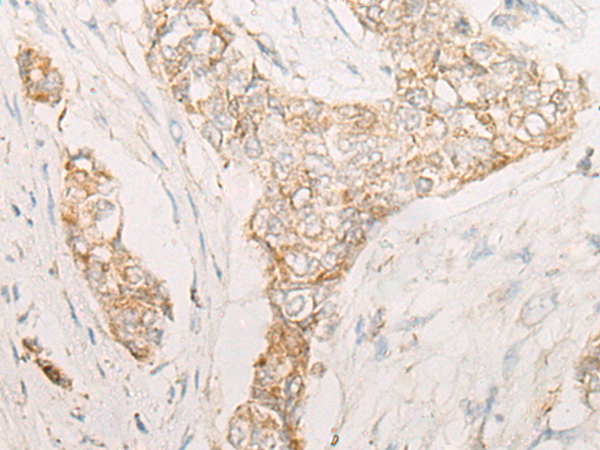

分类: 科研抗体货号: P06470别名: EVI1; MDS1; KMT8E; PRDM3; RUSAT2; MDS1-EVI1; AML1-EVI-1应用: WB,IHC反应种属: Human, Mouse